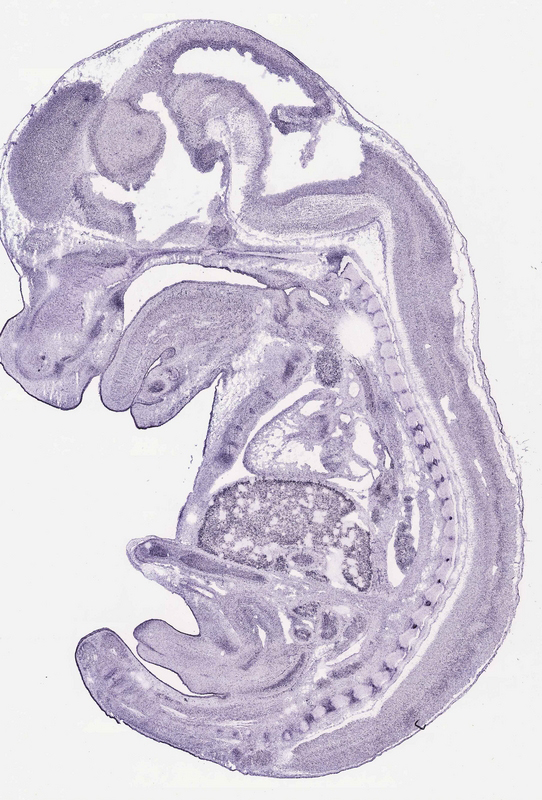

Specimen

euxassay_001650_01:

embryonic day 14.5

euxassay_001650_02: